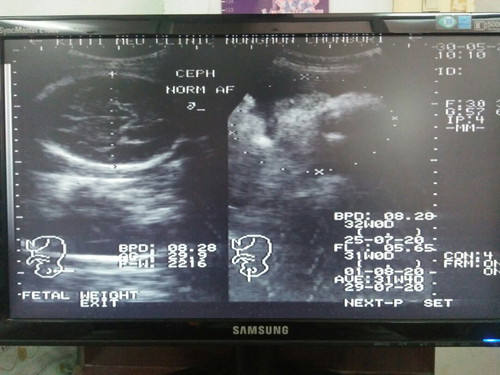

หมอบอกว่าน้ำหนักน้องเยอะเลย น้องตัวโตนะเนี่ย32wจะอยู่ที่โลครึ่ง แต่น้องบ้านนี้2,216???กลัวน้องหนักกว่านี้เพราะแม่ค่อนข้างตัวเล็กกลัวจะคลอดเองไม่ได้ ไม่อยากผ่า ก่อนท้องหนัก40 ปัจจุบันนี้หนัก56แล้ว มีแม่ๆคนไหนตัวเล็กแล้วคลอดธรรมชาติบ้างคะ(ส่วนคนที่ถามว่าท้องเท่านี้ๆท้องเล็กไปไหม ลูกจะตัวเล็กหรือเปล่า อยากให้โฟกัสที่น้ำหนักลูกค่ะ ไปซาวด์แล้วก็ถามหมอเลยค่ะว่าน้ำหนักลูกอยู่ในเกณฑ์ไหม ซาวด์ทุกครั้งที่หมอนัดนะคะจะได้รู้น้ำหนักลูกด้วย)